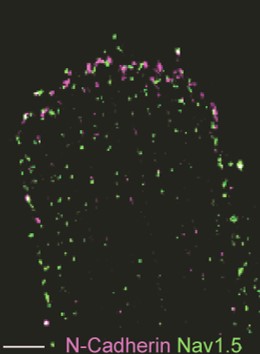

Distinct subcellular pools of Nav1.5-based sodium channels within the cardiomyocyte have been demonstrated, in particular at the intercalated disc and lateral membrane regions. Within these domains, Nav1.5 channels are not homogeneously distributed but rather grouped in clusters of various sizes and densities. Furthermore, different interacting proteins associate with Nav1.5 at these distinct subcellular domains, and are thought to contribute to the differences in channel density and/or kinetics observed between these areas. Sodium channels located at the lateral membrane are associated with the syntrophin-dystrophin complex. We have previously shown that mice lacking the last three amino acids of Nav1.5 essential for the interaction with the syntrophin-dystrophin complex show sodium current reduction exclusively at the lateral membrane (Shy et al. Circulation 2014). Nav1.5 channels in the intercalated disc region (which is devoid of syntrophin) interact with SAP97, plakophilin-2, desmoglein-2 and coxsackie and adenovirus receptor (CAR).

We have demonstrated that in mice with reduced expression of CAR (a cell adhesion protein enriched at the intercalated disc), sodium current was preferentially reduced at the intercalated disc region associated with increased arrhythmia inducibility during myocardial ischemia (Marsman et al. JACC 2014). Overall, little is still known about the specific roles for these separate pools of channels or their functional relevance during (patho)physiological conditions. Moreover, the consequences of subcellular diversity in sodium channel composition and function for disease severity and expressivity of SCN5A mutations form a challenging topic for future investigations.